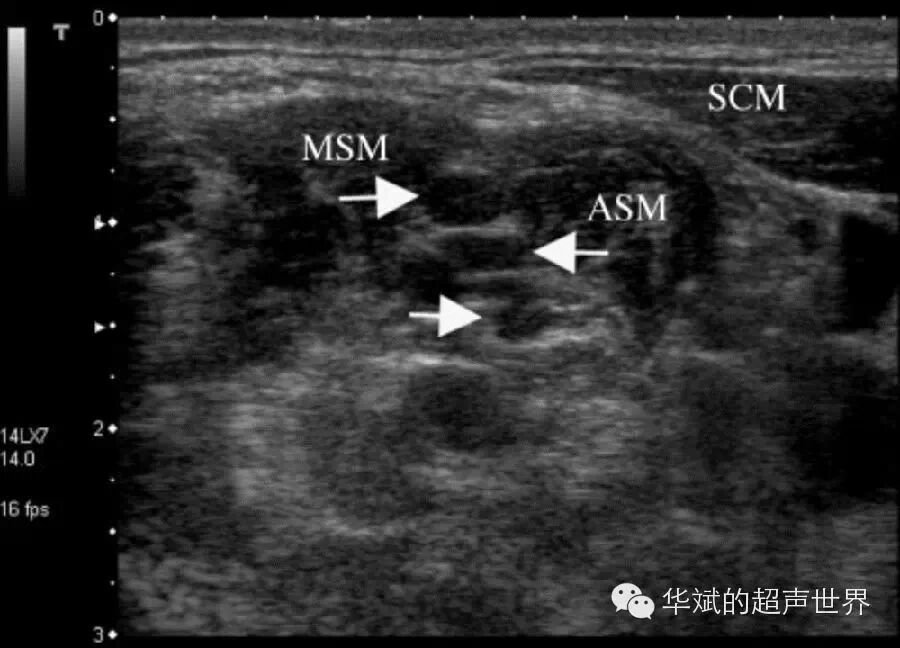

靠近神经根部的脊神经由椎间孔发出时一段主干通常为低回声。如臂丛神经位于横突前后结节间沟处和位于肌间沟处的神经束均呈低回声(图2)。

2 颈部肌间沟处臂丛神经主干,显示为低回声结构。箭头:臂丛神经,MSM:中斜角肌,ASM:前斜角肌,SCM:胸锁乳突肌